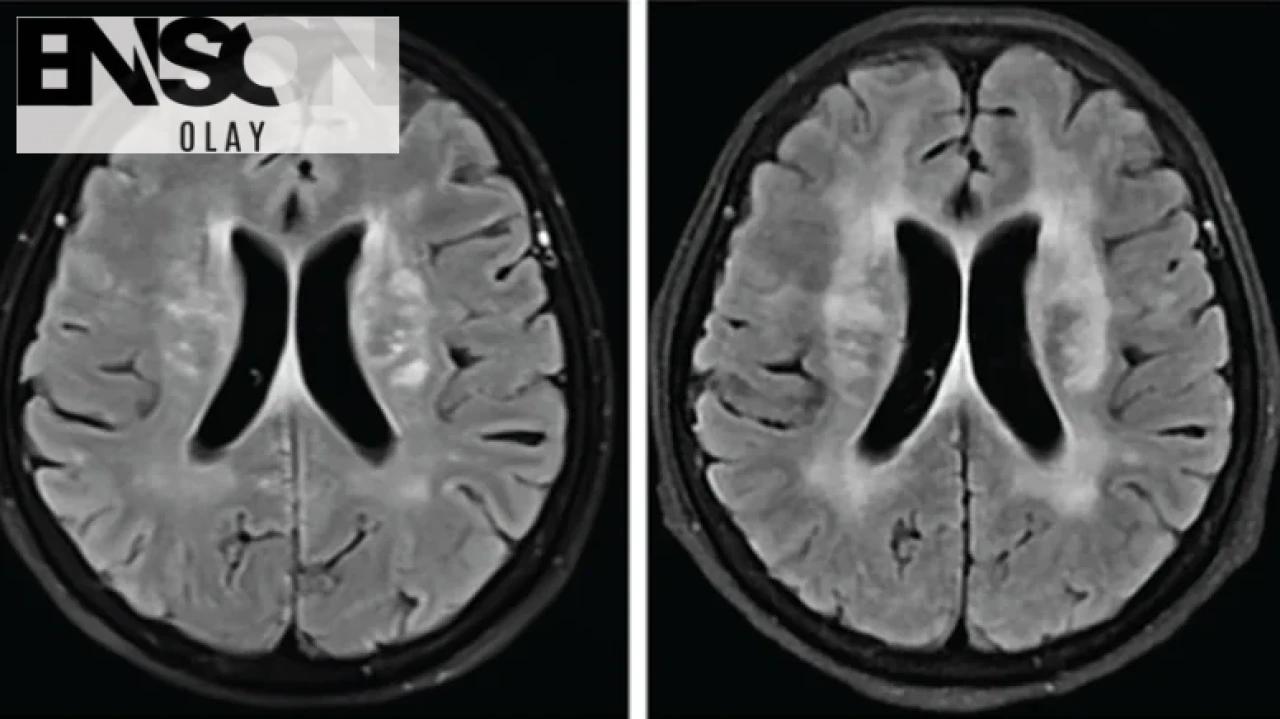

Doktorlar, kadının durumunu inceledikten sonra öncelikle menenjit şüphesiyle hareket etti. Yapılan MR sonucunda beyinde birçok lezyon tespit edildi ve bu durum enfeksiyon olasılığını artırdı. Ancak, antibiyotik tedavisine rağmen hastanın durumu iyileşmedi.

Hastaya hemen antiparaziter ilaç olan albendazol verildi. İki hafta içinde konuşma yetisini geri kazanan kadının sağlık durumu hızla düzelmeye başladı. Dört ay sonra yapılan kontrollerde beyindeki lezyonların büyük ölçüde küçüldüğü ve hastanın neredeyse tamamen iyileştiği görüldü.